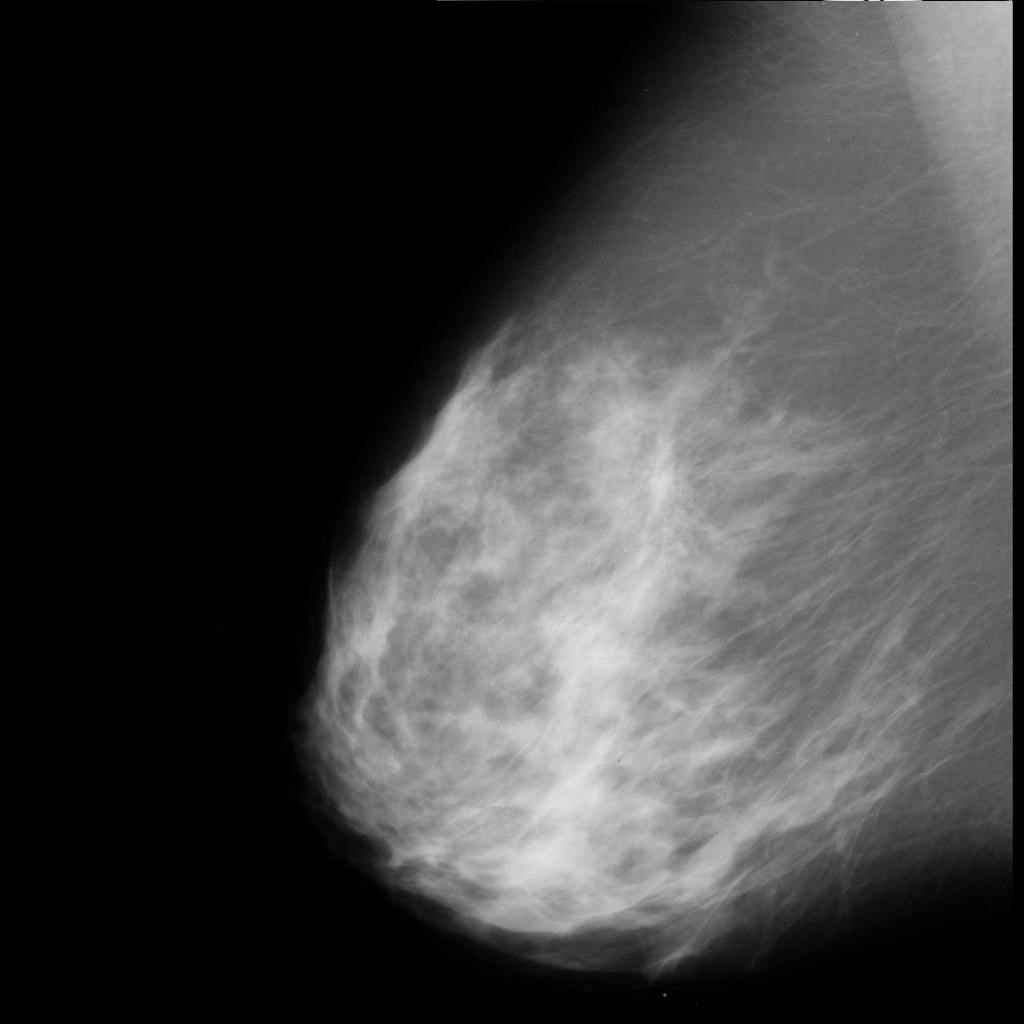

benign